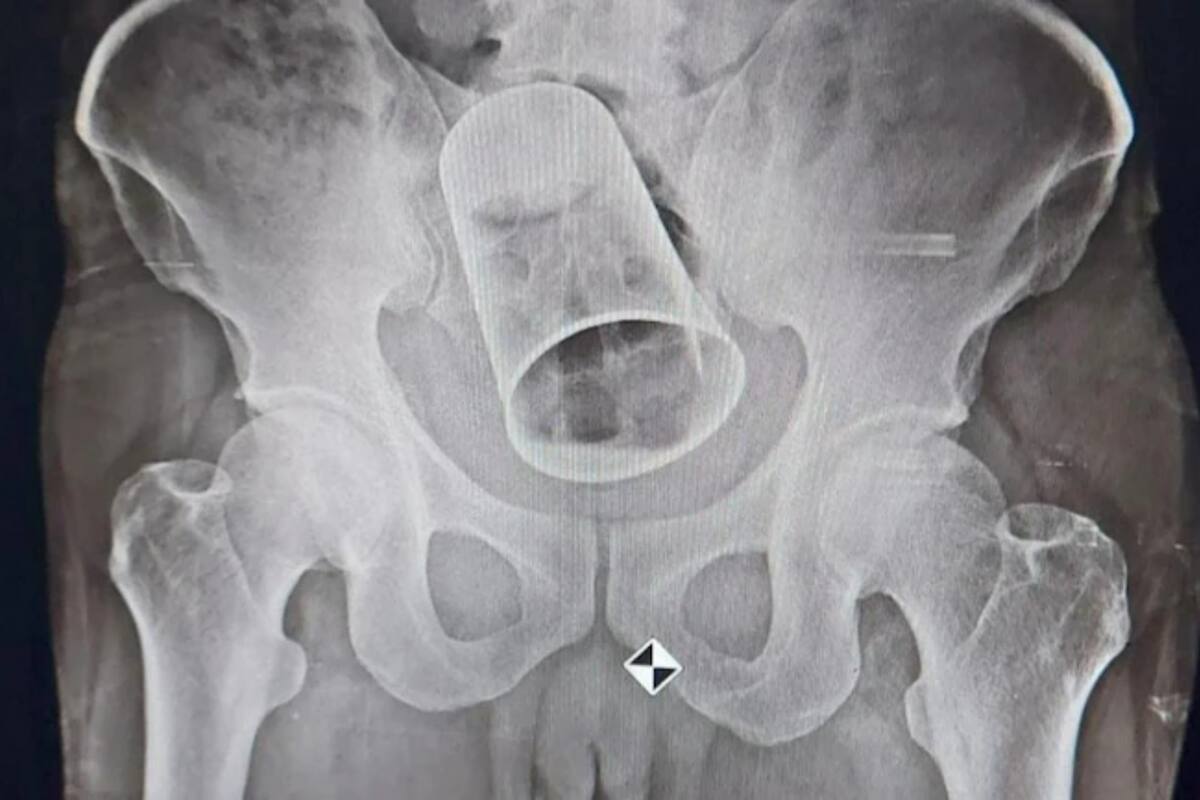

Una radiografía, elaborada en el MKCG Medical College And Hospital, situado en la ciudad de Brahmapur, exhibió la gravedad de la obstrucción cuando la copa fue hallada en su intestino. Aunque los médicos intentaron un método menos invasivo, tuvieron que recurrir a la cirugía para no ocasionar mayores problemas porque su estado de salud era grave en ese momento. Luego de dos horas y media de trabajo, tiempo el que cortaron una parte del intestino, consiguieron extraer la copa y salvar la vida del paciente.

El hombre incluso viajó a su ciudad natal en lugar de atenderse en Surat, Gujarat, y el objeto de 15 centímetros de largo y 8 de diámetro estuvo en su cuerpo durante diez días. El afectado no había querido reportar el hecho por temor a ser juzgado, pese a que no había podido evacuar debido la obstrucción y ya experimentaba severos dolores de estómago. Según información de medios locales, sus familiares lo llevaron al hospital cuando su estómago comenzó a hincharse y el riesgo de una infección creció. Pero no reveló la ubicación del vaso al equipo médico hasta que los estudios de imagen lo descubrieron.